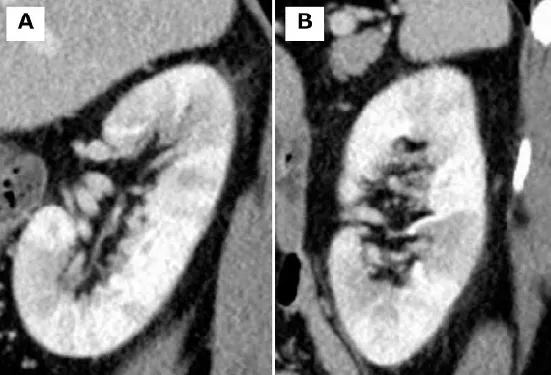

Uma causa incomum de hematúria glomerular intermitente!

Hematúria pós infecção, caso clínicos para auxiliar no entendimento de causas glomerulares comuns e raras...